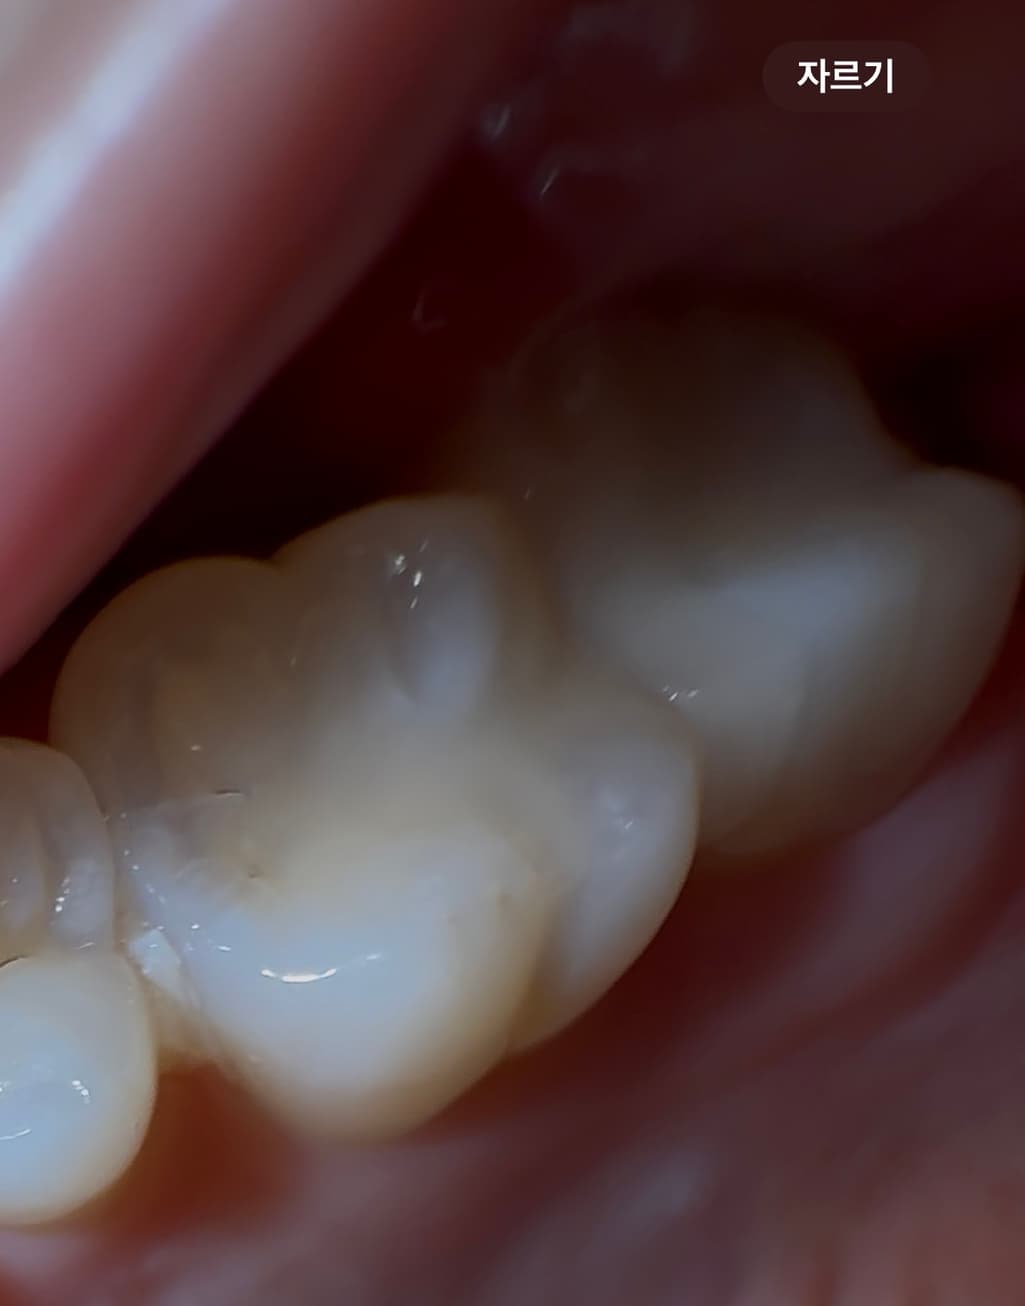

어금니 두개 인레이 했는데요 인레이 후 한달정도는 괜찮았는데 갑자기 음식 씹을때 시려워요.. 이거 크랙인가요? 하......

• 1번 째 사진

사진상으론 특별히 인레이 보철물에 어떤 이상이 있다고 단정하긴 어렵습니다. 치과가서 교합조정해보고 증상 지켜봐야 할 것 같습니다 크랙이면 주로 씹을때 치아가 찌릿합니다